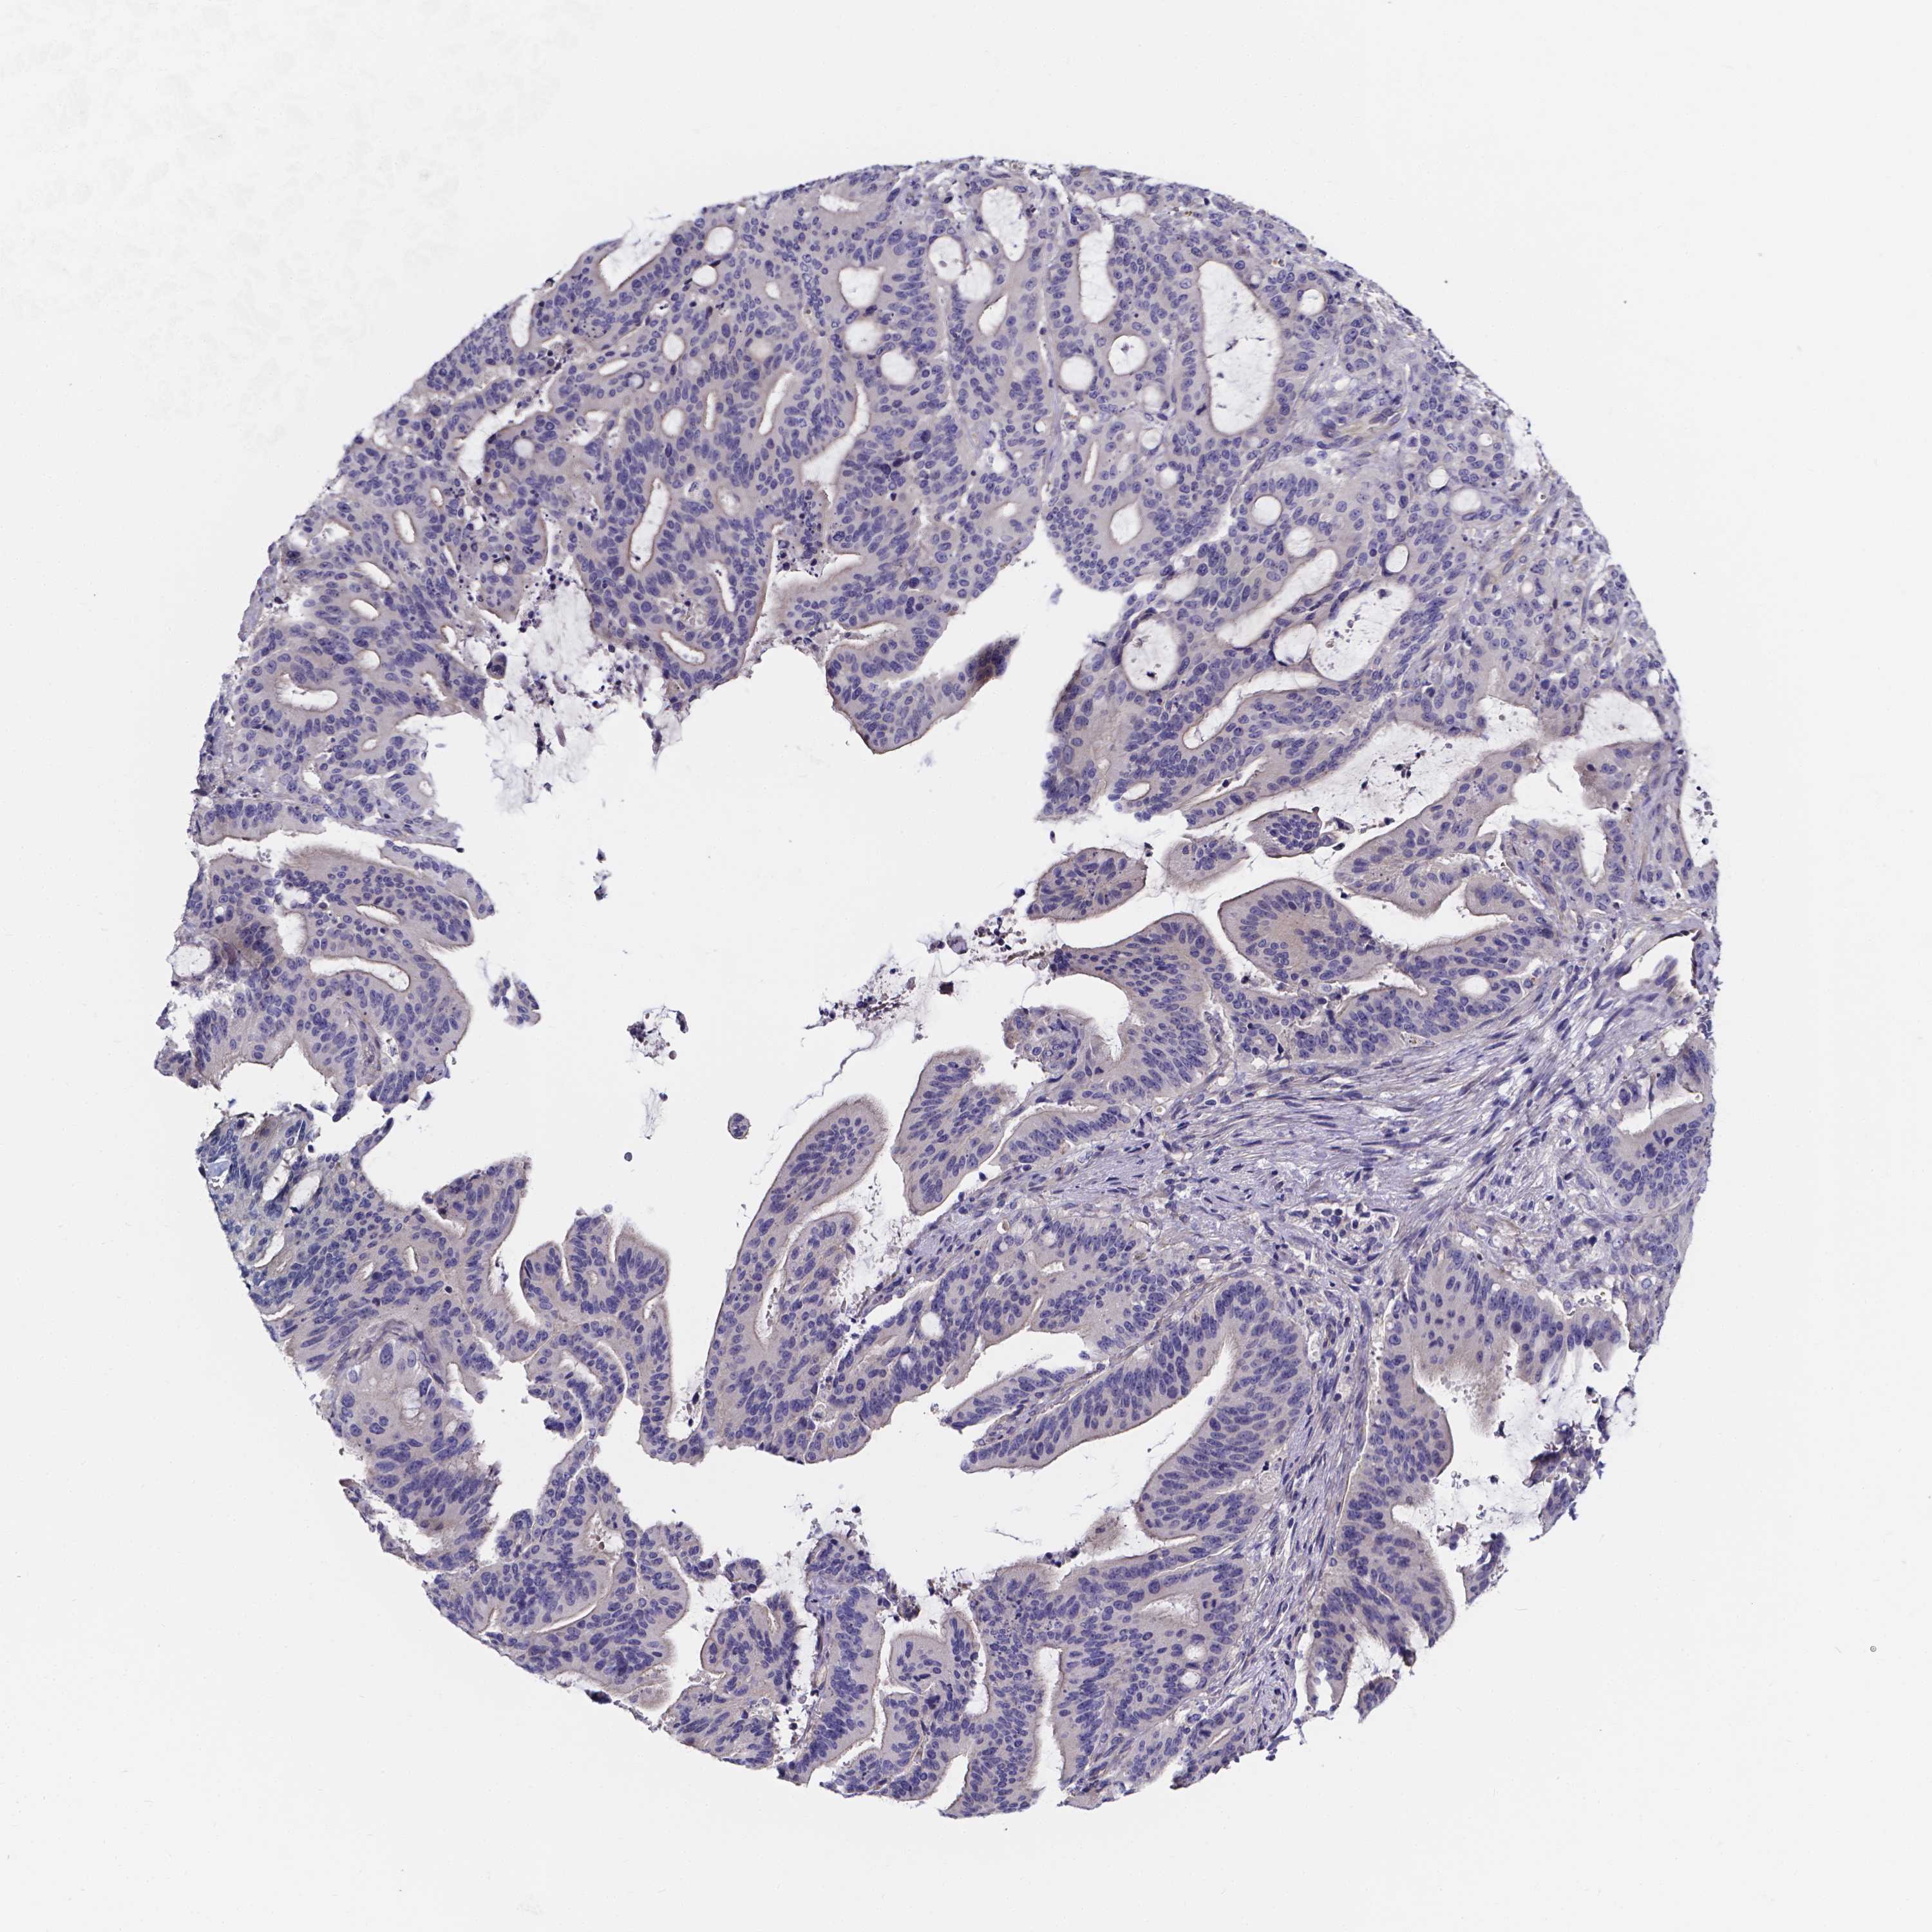

LIVER CANCER - Protein expressioni

A mouse-over function shows sample information and annotation data. Click on an image to view it in a full screen mode. Samples can be filtered based on level of antibody staining by selecting one or several of the following categories: high, medium, low and not detected. The assay and annotation is described here.

Note that samples used for immunohistochemistry by the Human Protein Atlas do not correspond to samples in the TCGA dataset.

Antibody stainingi

Antibody staining in the annotated cell types in the current human tissue is reported as not detected, low, medium, or high, based on conventional immunohistochemistry profiling in selected tissues. This score is based on the combination of the staining intensity and fraction of stained cells.

Each image is clickable and will lead to virtual microscopy that enables deeper exploration of all samples and also displays staining intensity scores, fraction scores and subcellular localization as well as patient and tissue information for each sample.

Antibody HPA041351

Staining

High

Medium

Low

Not detected

Intensity

Strong

Moderate

Weak

Negative

Quantity

>75%

75%-25%

<25%

None

Location

Nuclear

Cytoplasmic/membranous

Cytoplasmic/membranous,nuclear

Carcinoma, Hepatocellular, NOS

Cholangiocarcinoma